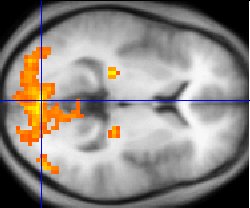

Sample fMRI data

This example of fMRI data shows regions of activation including primary visual cortex (V1, BA17), extrastriate visual cortex and lateral geniculate body in a comparison between a task involving a complex moving visual stimulus and rest condition (viewing a black screen). The activations (yellow-red) are shown (as is typical) against a background based on the average structural images from the subjects in the experiment.